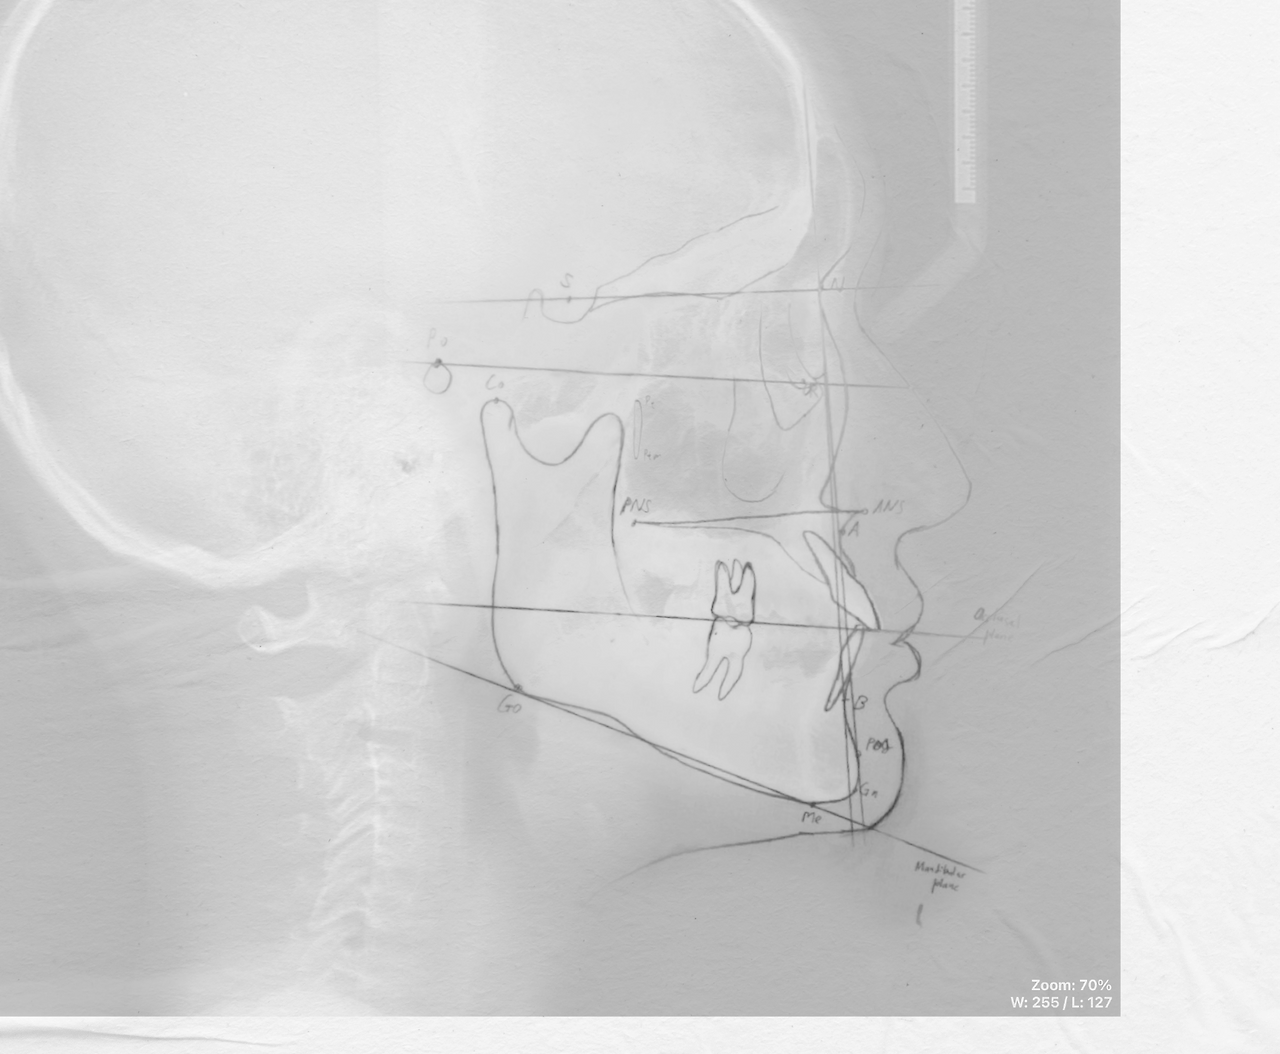

paper_landmark.png 정통적인 방법, 방사선 필름 위 트레이싱 종이를 얹어 연필로 구조물과 계측점을 직접 계측한 예시를 재구성한 이미지입니다.

교정분석을 하기 전, 촬영된 측면 두부 X-ray 영상에서 교정학적으로 중요한 포인트들을 표시하고 각도나 거리 등을 계측하여 수치화해야 하는데요. 과거에는 필름으로 사진을 뽑아 속이 비치는 얇은 종이(트레이싱 종이)를 얹고 설계도를 그리듯 치과 전문의가 직접 연필로 그림을 그려가며 자와 각도기 등을 통해 수치를 측정하였습니다. 보통 20분 ~ 30분 정도 걸리는 과정을 거치다 보니 치과 전문의 인력이 많이 투입되는 일이었습니다.